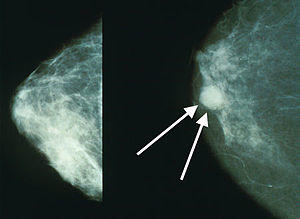

Mammo breast cancer wArrows.jpg

Mammograms showing a normal breast (left) and a breast with cancer (right)